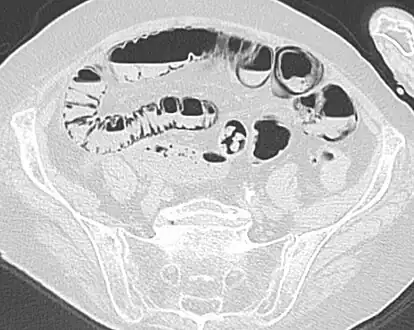

Pneumatosis intestinalis in computed tomography with intestinal ischemia. Lung window for better representation of the gas deposits in the intestinal walls.- Upright AP radiograph showing gas in the wall of the small bowel in the left upper quadrant indicative of pneumatosis intestinalis.

- Coronal reformatted MDCT image showing extensive pneumatosis intestinalis in the left upper quadrant small bowel. The pneumatosis is more cystic and nodular in the small bowel in the midline and the right of midline. This patient had a relatively benign presentation without bowel ischemia and was treated conservatively.